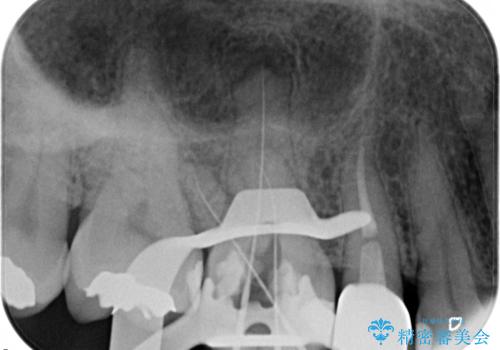

- 定期検診にて、奥歯の頬側歯肉にサイナストラクトが発見された患者様です。

根管治療から歯冠修復まで行っております。

サイナストラクト(瘻孔)から原因歯を特定し治療を行っております。根管治療を行った歯牙は破折リスクが高くなるため被せものによる治療を提案しております。